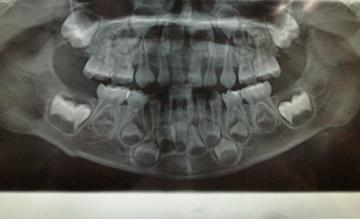

下面是患者在国外(澳大利亚)拍的X线片

患儿口腔全景片